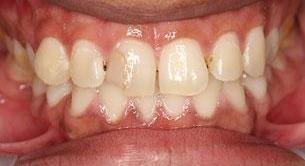

This young dad had four congenitally missing upper teeth. He had a quick orthodontic treatment and a large span bridge placed in as a teenager. He never smiles with teeth showing.

After many years of wear and tear, some of the work started to break and fail. We removed the defective bridges, managed to save all the existing teeth and placed four implant supported crowns in. The patient is very happy to be able to smile confidently now.